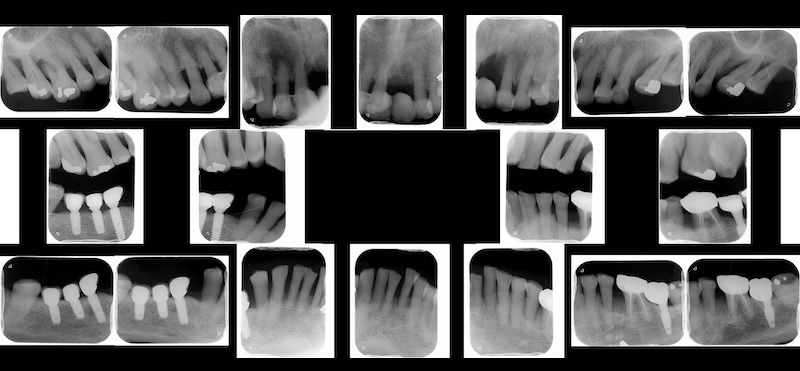

初步進行口內檢查,搭配環口式 X 光片和左上正中門齒的局部 X 光片評估。我的診斷是全口嚴重牙周病,且左上正門齒的齒槽骨破壞已經超過牙根尖端,屬於牙周病的無救牙,位置也己經很不理想,不得已只能建議拔牙。

在做美容重建之前,首先會把牙周病控制穩定。現在我的水雷射牙周病治療全程都使用顯微鏡,目標就是要把第一階段非手術的療程做得更好,同時減低第二階段手術治療的必要性。

此外,也會利用口內掃描的方式製作牙齒護套,下顎門齒區則用 Ribbond 做好齒間固定。這些措施的主旨是鎖定現在的牙齒相對位置,避免她的牙齒再繼續位移。

顯微牙周治療結合水雷射,比傳統治療更精準、微創、快速。有興趣的朋友可以參考:微創顯微水雷射牙周治療是什麼?